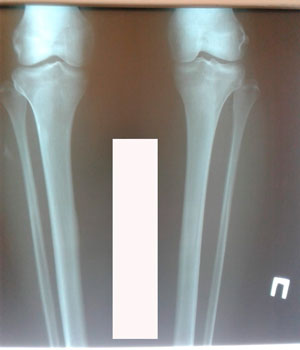

Исходник - 38 лет.

Дата операции - 18.02.2020

IMG_8958-18-02-20-08-08.JPG

IMG_8963-18-02-20-08-08.JPG